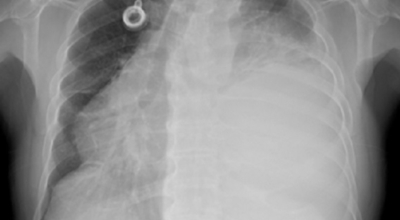

폐암 검사는 X-ray를 통해서 검사하는데 , 크기가 작거나 구석에 위치한 경우 확인이 어려운 경우도 있습니다. 그리고 조직 검사를 통해서 정확한 진단을 하게 돼요. 폐암이 발견되면 종양의 크기나 전이 여부 , 위치에 따라서 수술 여부를 결정하게 되어요.